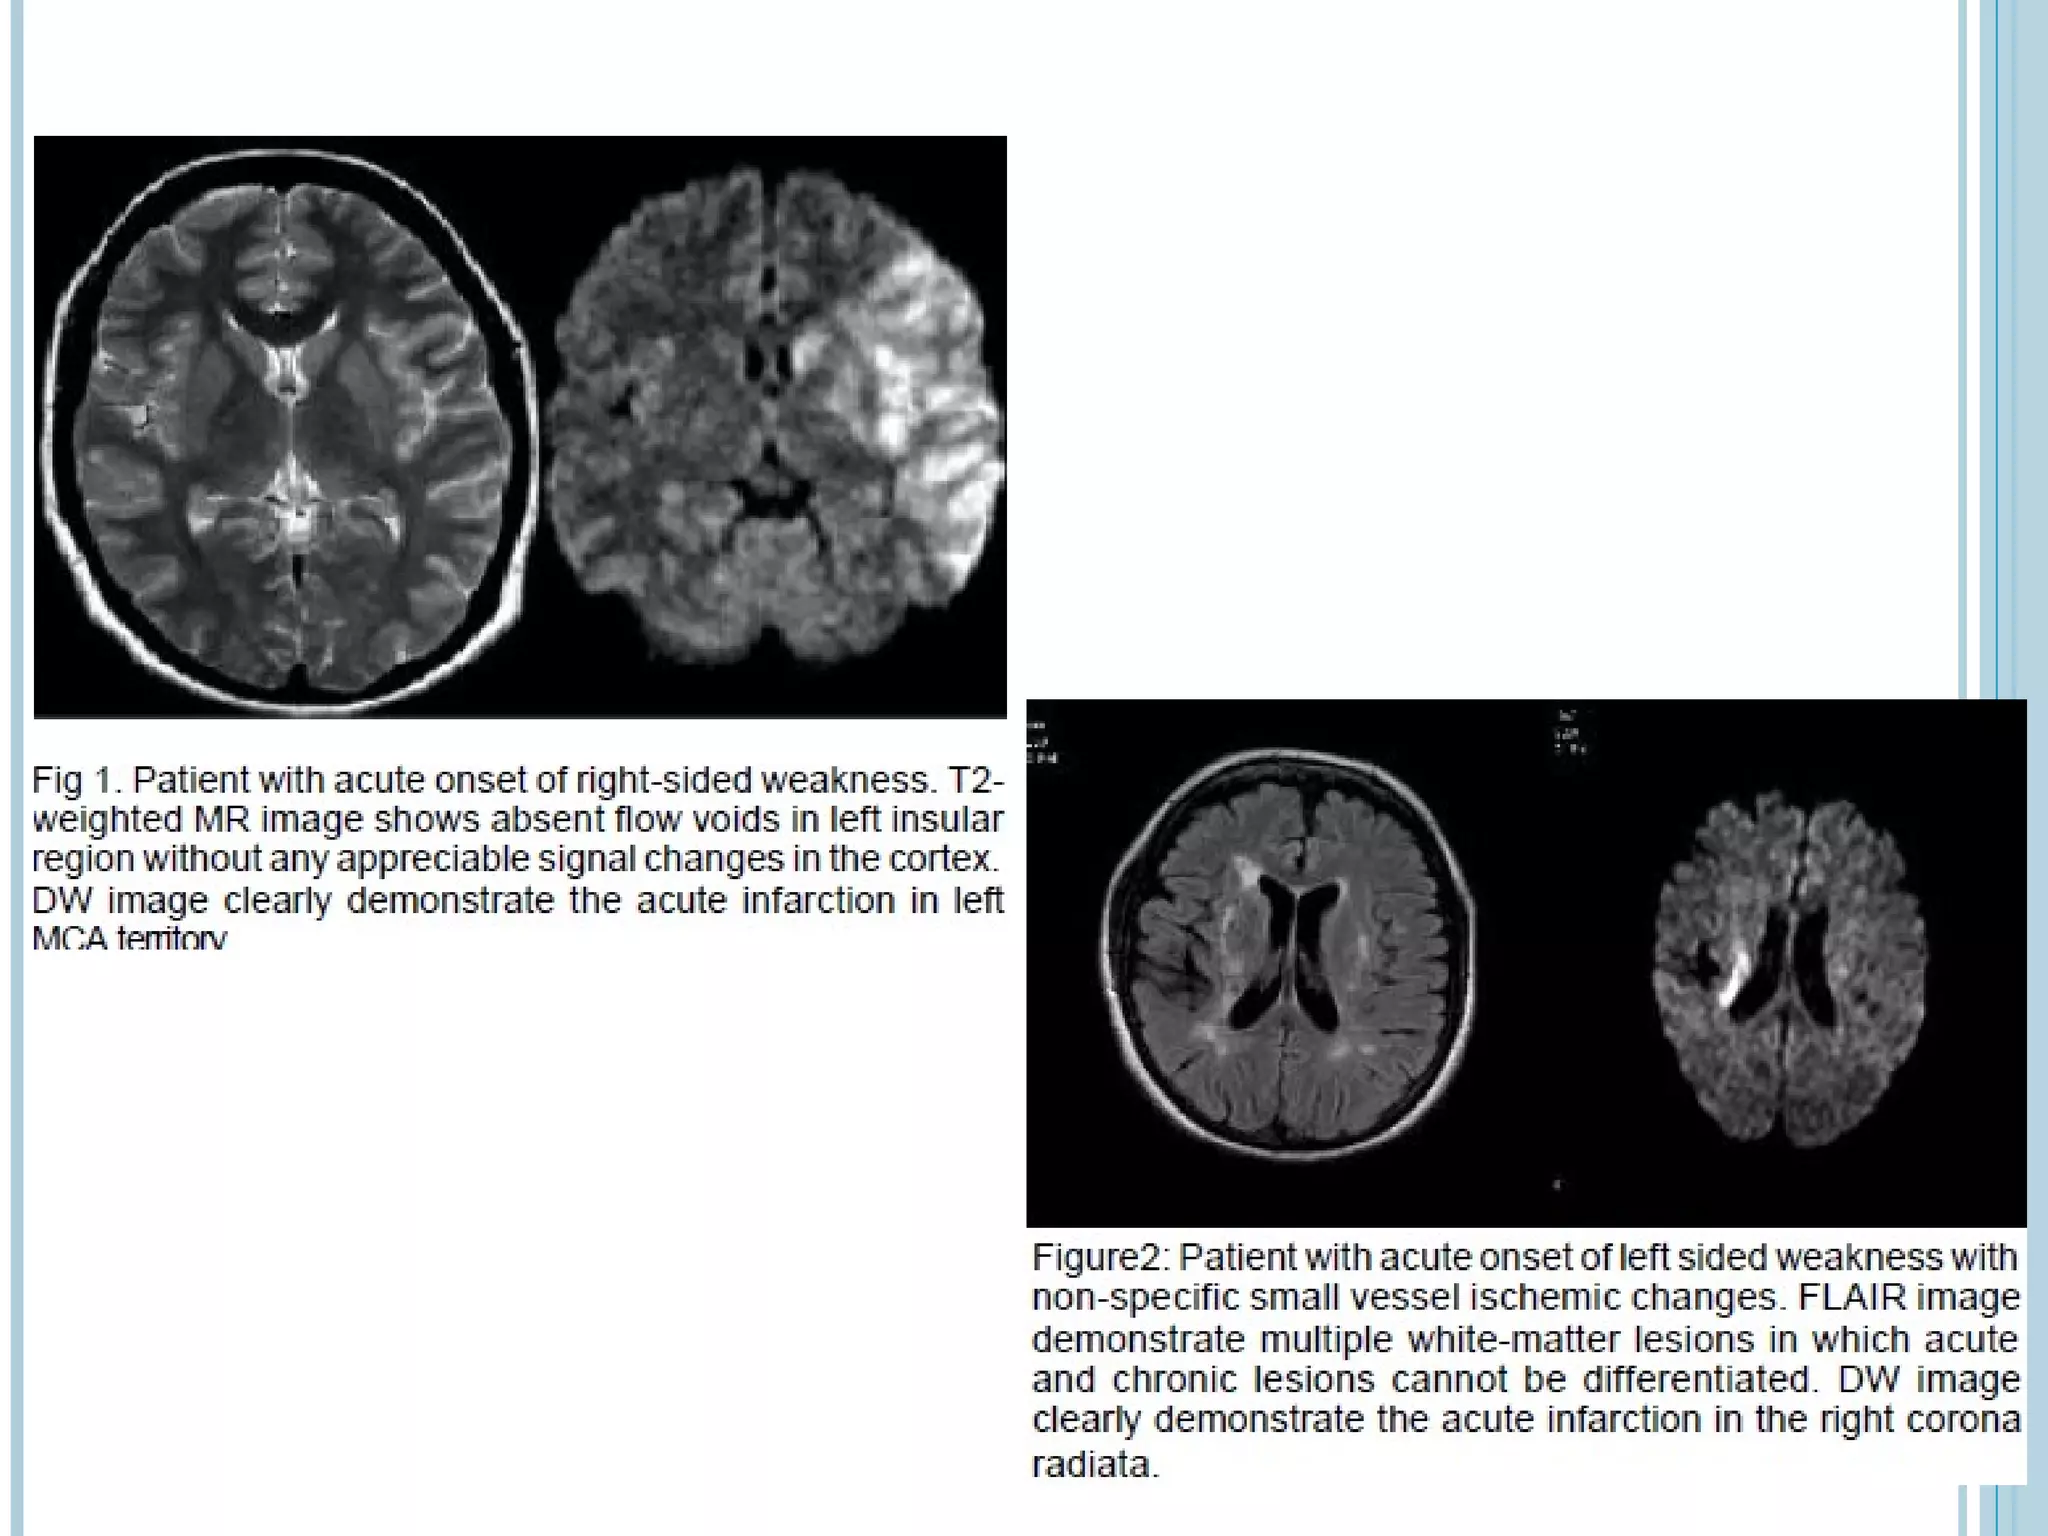

EVALUATION OF ACUTE STROKE ON DWI

   The DWI and ADC maps show changes in ischemic brain

within minutes to few hours

   The signal intensity of acute stroke on DW images increase

during the first week after symptom onset and decrease

thereafter, but signal remains hyper intense for a long period

(up to 72 days in the study by Lausberg et al)

   The ADC values decline rapidly after the onset of ischemia and

subsequently increase from dark to bright 7-10 days later .

   This property may be used to differentiate the lesion older

than 10 days from more acute ones (Fig 2).

EVALUATION OF ACUTESTROKE ON DWI  The DWI and ADC maps show changes in ischemic brain within minutes to few hours  The signal intensity of acute stroke on DW images increase during the first week after symptom onset and decrease thereafter, but signal remains hyper intense for a long period (up to 72 days in the study by Lausberg et al)  The ADC values decline rapidly after the onset of ischemia and subsequently increase from dark to bright 7-10 days later .  This property may be used to differentiate the lesion older than 10 days from more acute ones (Fig 2).  Chronic infarcts are characterized by elevated diffusion and appear hypo, iso or hyper intense on DW images and hyperintense on ADC maps